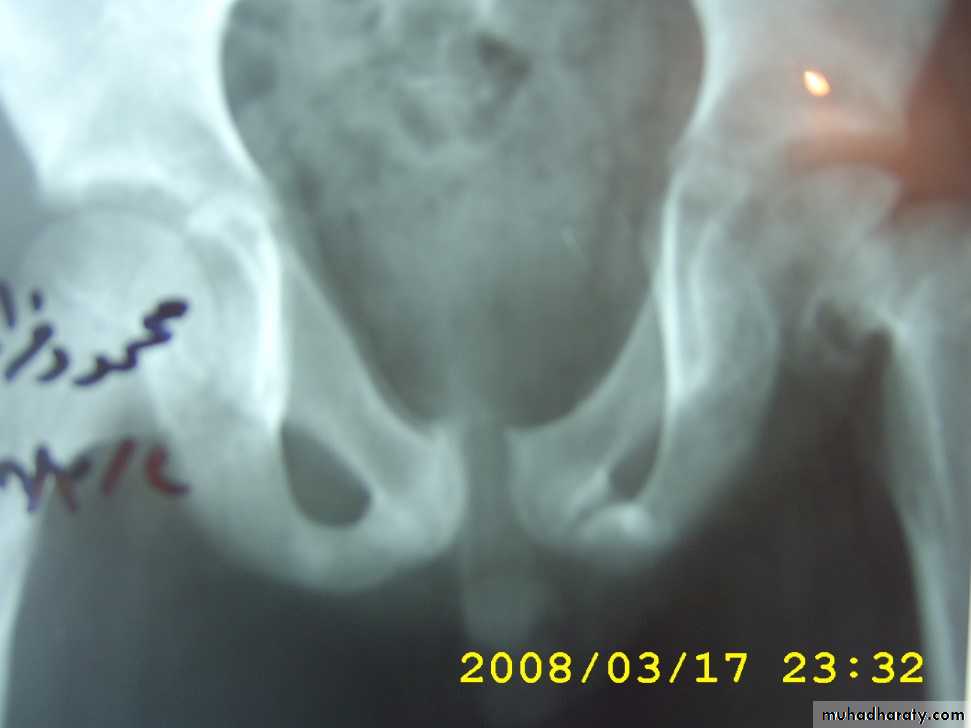

Pelvic fracture

Almost all posterior urethral injuries are caused by pelvic fracture from blunt trauma. Urethral injury occurs in 10% of men with pelvic fractures.

The diagnosis of posterior urethral injury is suggested by a history of pelvic fracture,

• Triad of pelvic fracture, blood at the meatus and inability to void are diagnostic of urethral injury